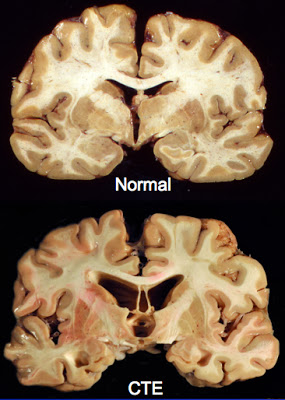

Dr. Robert Stern, co-director of the research group, and his colleagues uncovered elevated levels of tau protein in Duerson’s brain, clumped especially around its deep wrinkles, called sulci.

The typical brain afflicted with CTE will have a reduced brain volume, particularly in the frontal and temporal lobes. This reduction is associated with enlarged ventricles, or fluid-filled brain cavities.

Reduced blood flow and, eventually, atrophy to several key brain regions, including the amygdala (emotion) and hippocampus (memory formation) likely explains the physical and personality changes associated with the disease.

A view under the microscope reveals neuron loss, beta-amyloid peptide, and neurofibrillary tangles formed from deposits of tau protein—cornerstones of our current knowledge of Alzheimer’s.